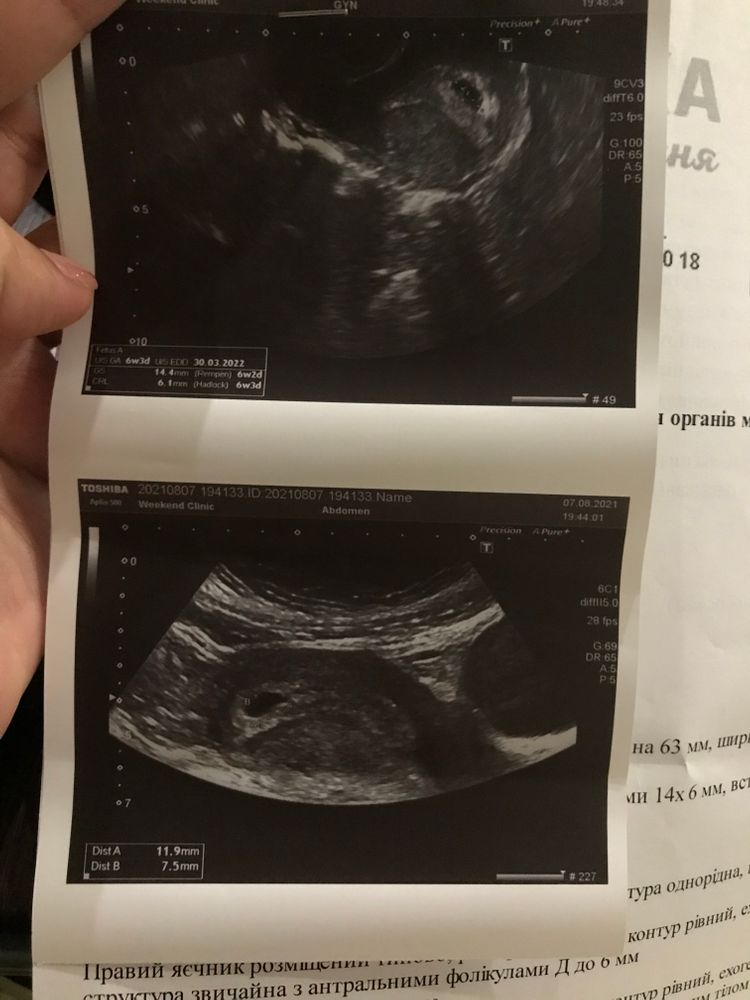

Узи на 36 ДЦ - плодное яйцо 3,3 мм ( 5 недель)

и Вот вчера ((( на 52 ДЦ - должно быть 7 недель 2 дня на УЗИ показало только ПЯ 14*6 и ЖМ 7,7 мм. ЖМ увеличен,это же плохо??? И нет эмбриона (((

У меня в 6+5 пя было 20 мм и жм 5 мм не было эмбриона,поставили под вопросом анэмбрионию,переделала через 2 дня в 7 ровно пя 22,6,жм 5,5 мм и пусто и контрольное через 3 дня в 7+3 пя 26 мм,жм 6,4 и пусто,врач сказала что уже не появится,жм большой, беременность патологическая,сделали медикаментозный аборт,через три цикла здоровая беременность,уже в 6+2 был эмбрион 5,4 мм и сб билось, переделайте УЗИ в другом месте